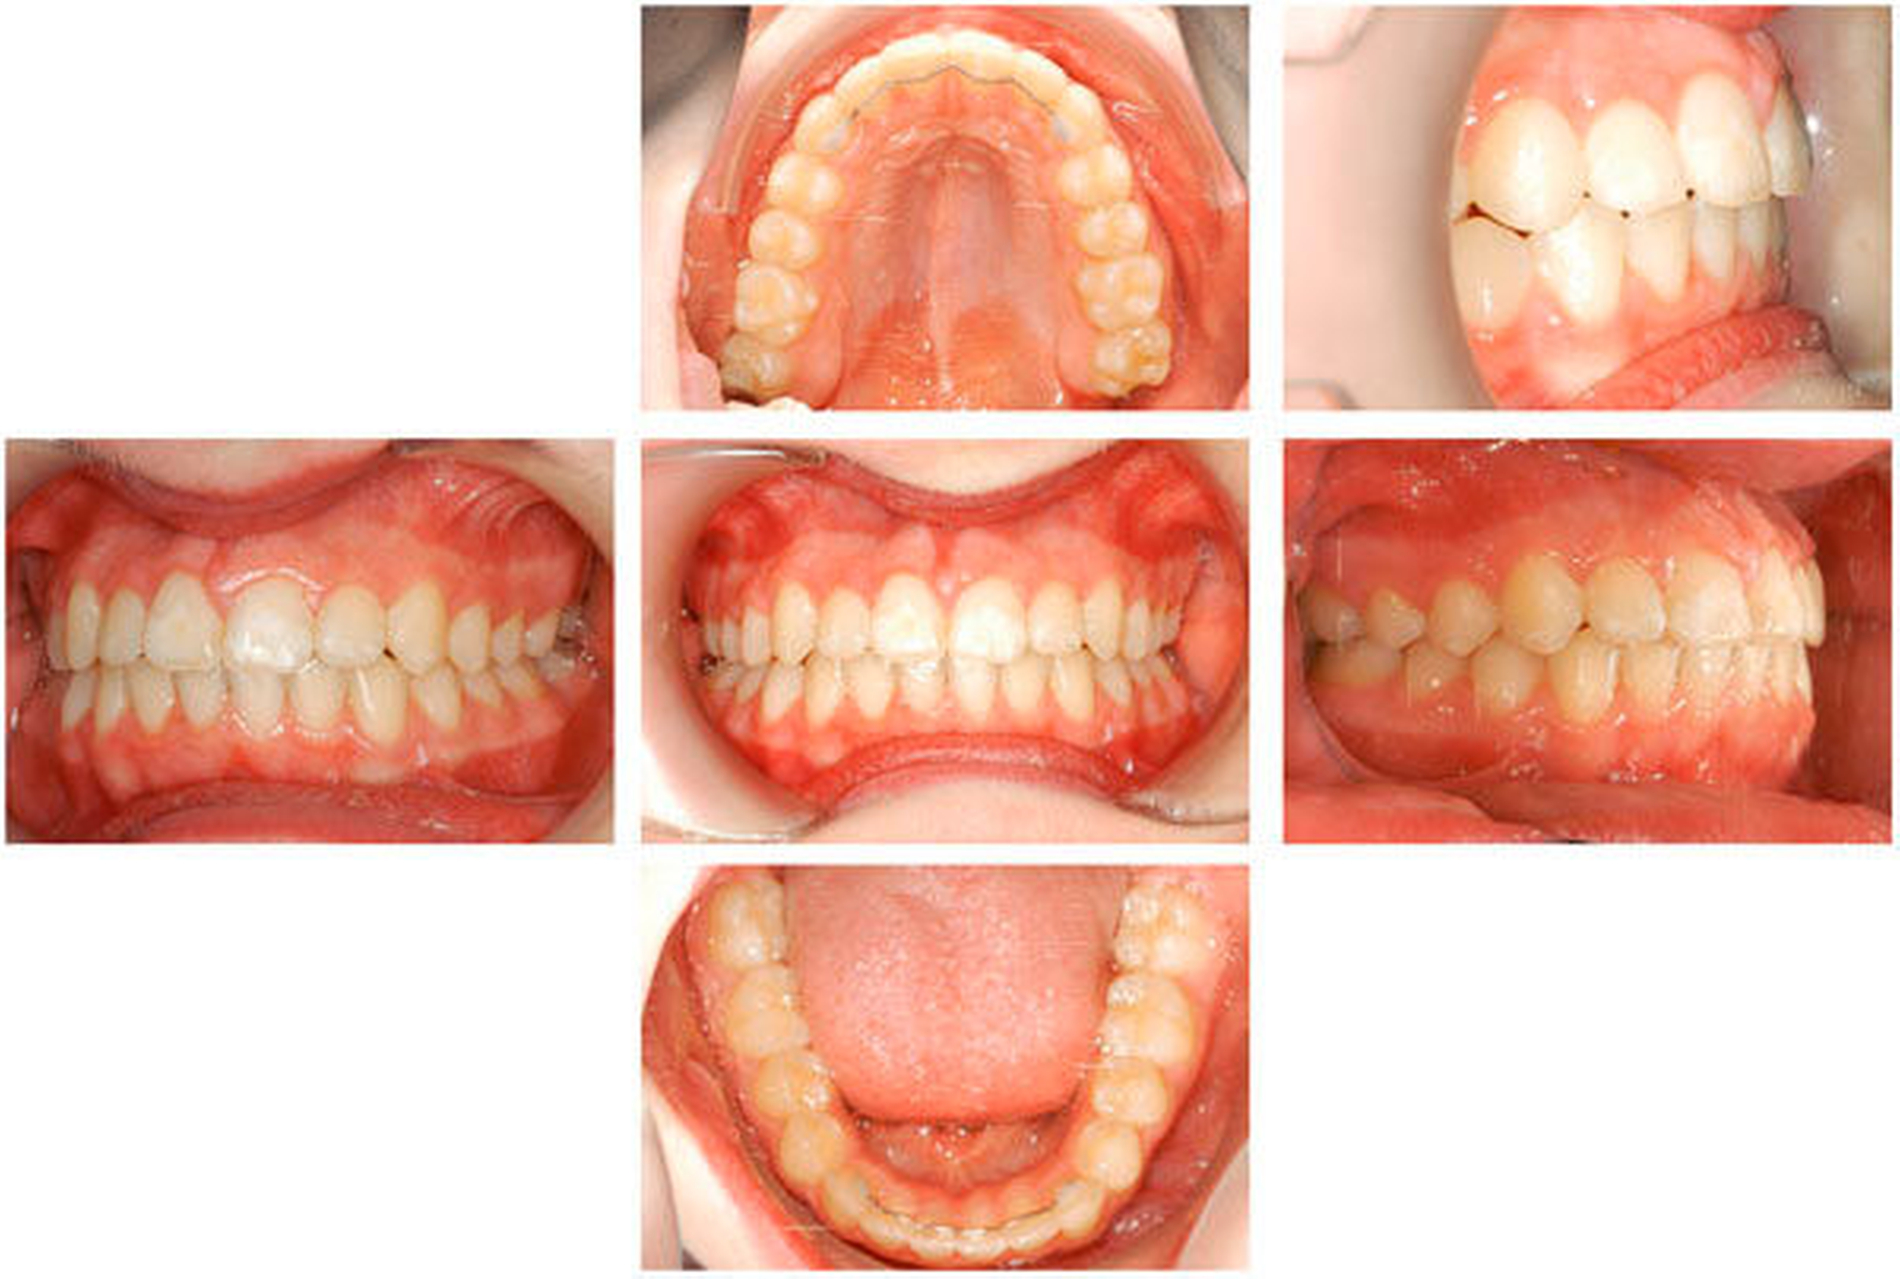

Das Prinzip einer CAD/CAM-gesteuerten Insertion wird anhand einer zehnjährigen Patientin mit einem Platzmangel für die oberen Eckzähne dargestellt (Abbildungen 4a, 4b). Die Behandlung begann mit dem Anpassen von Molarenbändern und einem Silikon-Abdruck des Oberkiefers, der mit dem FRS an das zahntechnische Labor gesendet wurde und dort mit dem FRS der Patientin überlagert wurde. So konnten geeignete Insertionsstellen virtuell geplant werden (Abbildungen 1, 2a, 2b). Nach Rücksprache mit dem Behandler bezüglich der Mini-Implantatpositionen erfolgte die Herstellung der Insertionsschablone (Abbildung 3). Parallel dazu wurde auch der Beneslider [Wilmes, 2010] hergestellt, der zusammen mit der Insertionsschablone geliefert wurde (Abbildung 5). Mithilfe der Insertionsschablone konnten die Mini-Implantate und der Beneslider im selben Termin eingesetzt werden (Abbildungen 6, 7a, 7b). Nach 10 Monaten Distalisierung waren die Molaren in der Zielposition und es war ausreichend Platz für die Eckzähne vorhanden (Abbildungen 8a, 8b), so dass Brackets für die zweite Phase der Behandlung eingesetzt werden konnten. Die Multibracket-Apparatur (Abbildung 9) konnte nach 12 Monaten entfernt werden (Abbildungen 10, 11).